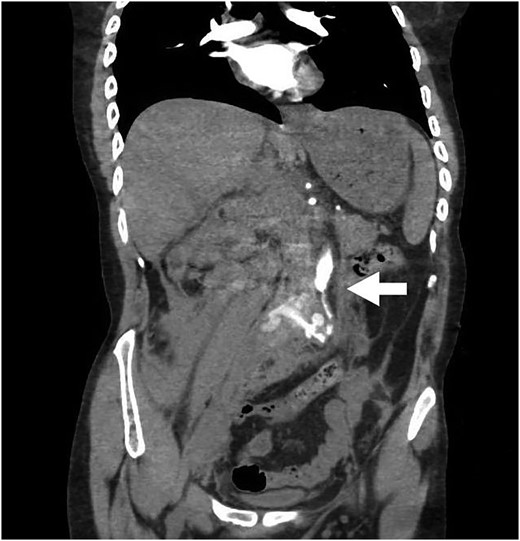

The patient returned to the hospital less than a week later in extremis. He had severe back pain and was diaphoretic. The patient was hypotensive and tachycardiac. He had no femoral pulses. Repeat CT scan revealed extension of the aortic injury in the abdominal aorta with no flow in the iliac (Figs 2–4). The patient was emergently taken to the operating room (OR) where the aorta, iliac and femoral vessels were unable to hold sutures. We were unable to repair this patient's aorta. Post-operatively, we spoke with the family, and the patient was allowed to expire.

Note contrast in the distal aorta but no contrast in the iliac arteries.